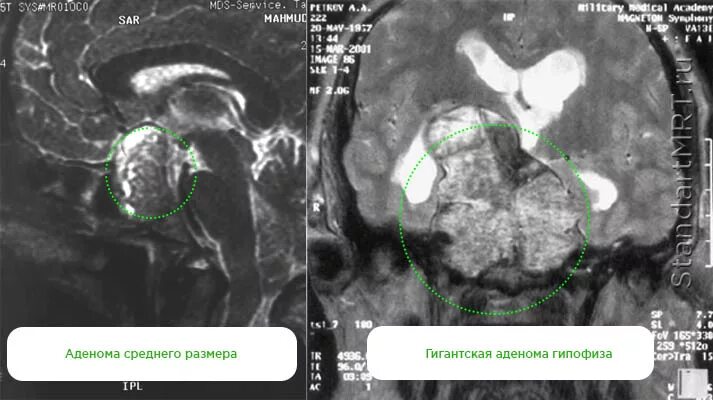

Макроаденома гипофиза